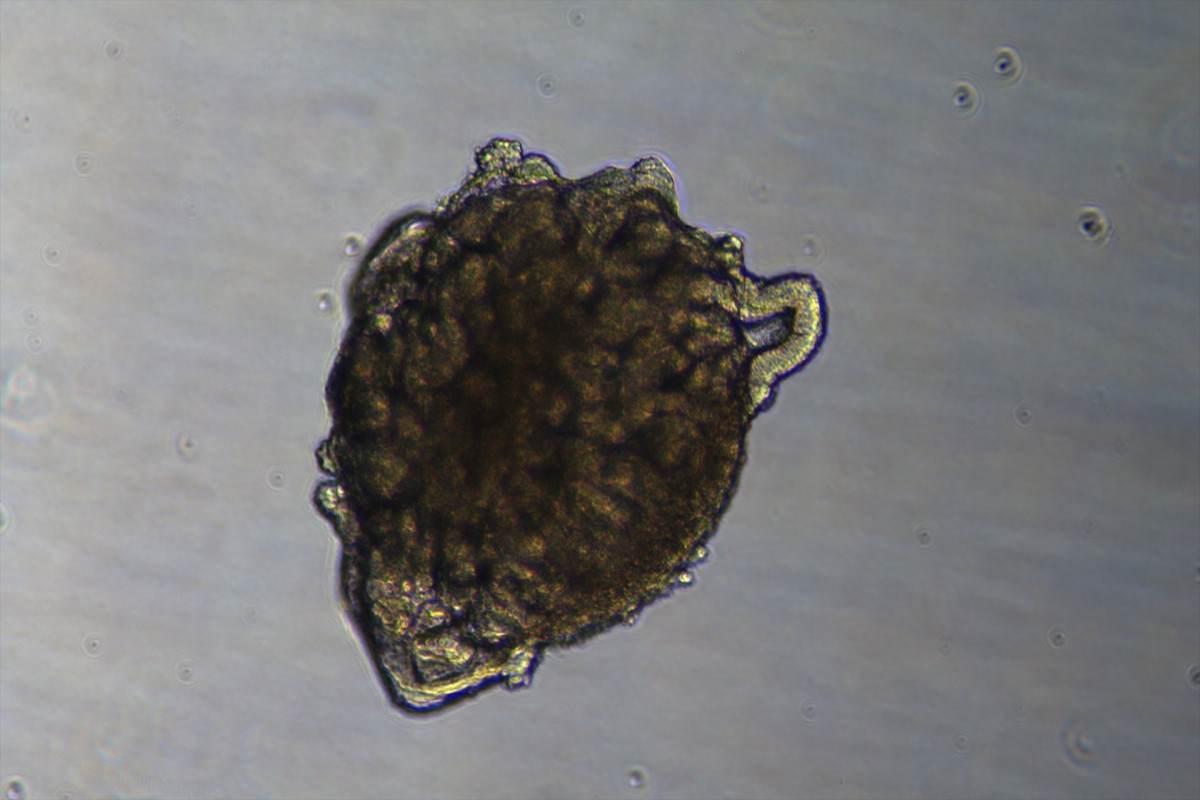

EuropaPress 7069897 imagen organoides

Imatge de organoides - IBEC

Un organoide de ronyó és una estructura tridimensional, de poques micres de mida, cultivada al laboratori a partir de cèl·lules mare humanes i, tot i que no és un òrgan complet, “reprodueix moltes de les seves estructures i funcions principals” i permet estudiar com es desenvolupa el ronyó.